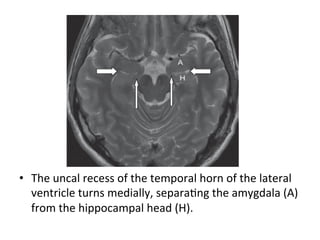

•  The	uncal	recess	of	the	temporal	horn	of	the	lateral

ventricle	turns	medially,	separaHng	the	amygdala	(A)

from	the	hippocampal	head	(H).

(A)	Amygdala	(large	arrow),	uncus	(short	arrow),	free	margin	of

tentorium	cerebelli	(thin	arrow).

(B)	Hippocampal	head	(large	arrow),	uncal	recess	of	temporal	horn	separaHng

posterior	aspect	of	amygdala	superiorly	from	hippocampal	head	inferiorly.

*Hippocampal	head	is	recognized	by	digitaHons	on	its	superior	surface.